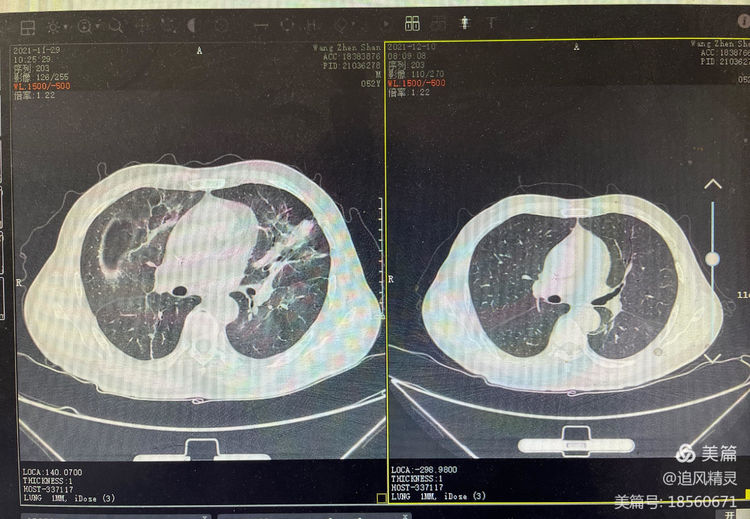

患者王某,男,现年65岁,颍东区插花镇农民,因淋巴瘤化疗后反复发热,先后到多家医院就诊,辗转一月余,经过各种检查以及高级抗菌药物应用均不见好转,后来到阜阳市第二人民医院感染科就诊,诊断明确为细菌真菌性疾病,治愈出院。像王某这样的病人阜阳市第二人民医院感染科近两年来已收治多例,此外,还有一些发热待查患者,最终也被明确诊断并治愈。